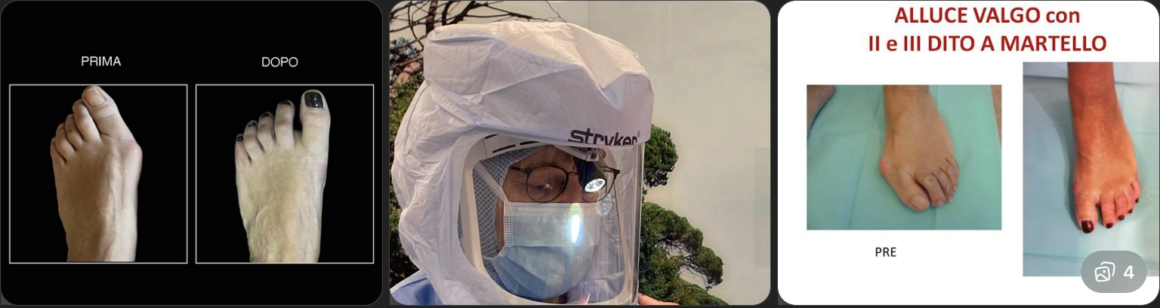

L’alluce valgo è una delle patologie più diffuse del piede e si presenta come una deformità progressiva dell’articolazione metatarso-falangea del primo dito. Questa condizione comporta una deviazione dell’alluce verso le altre dita, spesso accompagnata dalla comparsa della tipica “cipolla”, ovvero una prominenza ossea dolorosa sul lato interno del piede.

Il problema non è solo estetico, ma soprattutto funzionale, poiché può causare dolore durante la camminata, difficoltà nell’indossare calzature e limitazioni nelle attività quotidiane. Con il passare del tempo, se non trattato adeguatamente, l’alluce valgo può peggiorare e portare a complicazioni come infiammazioni croniche, callosità e sovraccarico delle altre dita.

Il Dr. Paolo Ceccarini a Perugia esegue una valutazione approfondita per individuare il grado della deformità e stabilire il trattamento più idoneo per ogni paziente. La diagnosi si basa su visita clinica accurata, analisi dell’appoggio plantare ed eventuali esami radiografici.

Quando invece la deformità è avanzata e provoca dolore persistente, si ricorre alla chirurgia. Il Dr. Ceccarini utilizza tecniche moderne e mini-invasive, che permettono di correggere l’allineamento dell’alluce con incisioni ridotte, minor trauma per i tessuti e tempi di recupero più rapidi.

- alluce valgo

- dita a martello

L’alluce valgo è una delle patologie più frequenti e consiste nella deviazione laterale dell’alluce, spesso associata a dolore e infiammazione. Le dita a martello, invece, sono deformità delle falangi che possono causare callosità dolorose e difficoltà nella deambulazione.